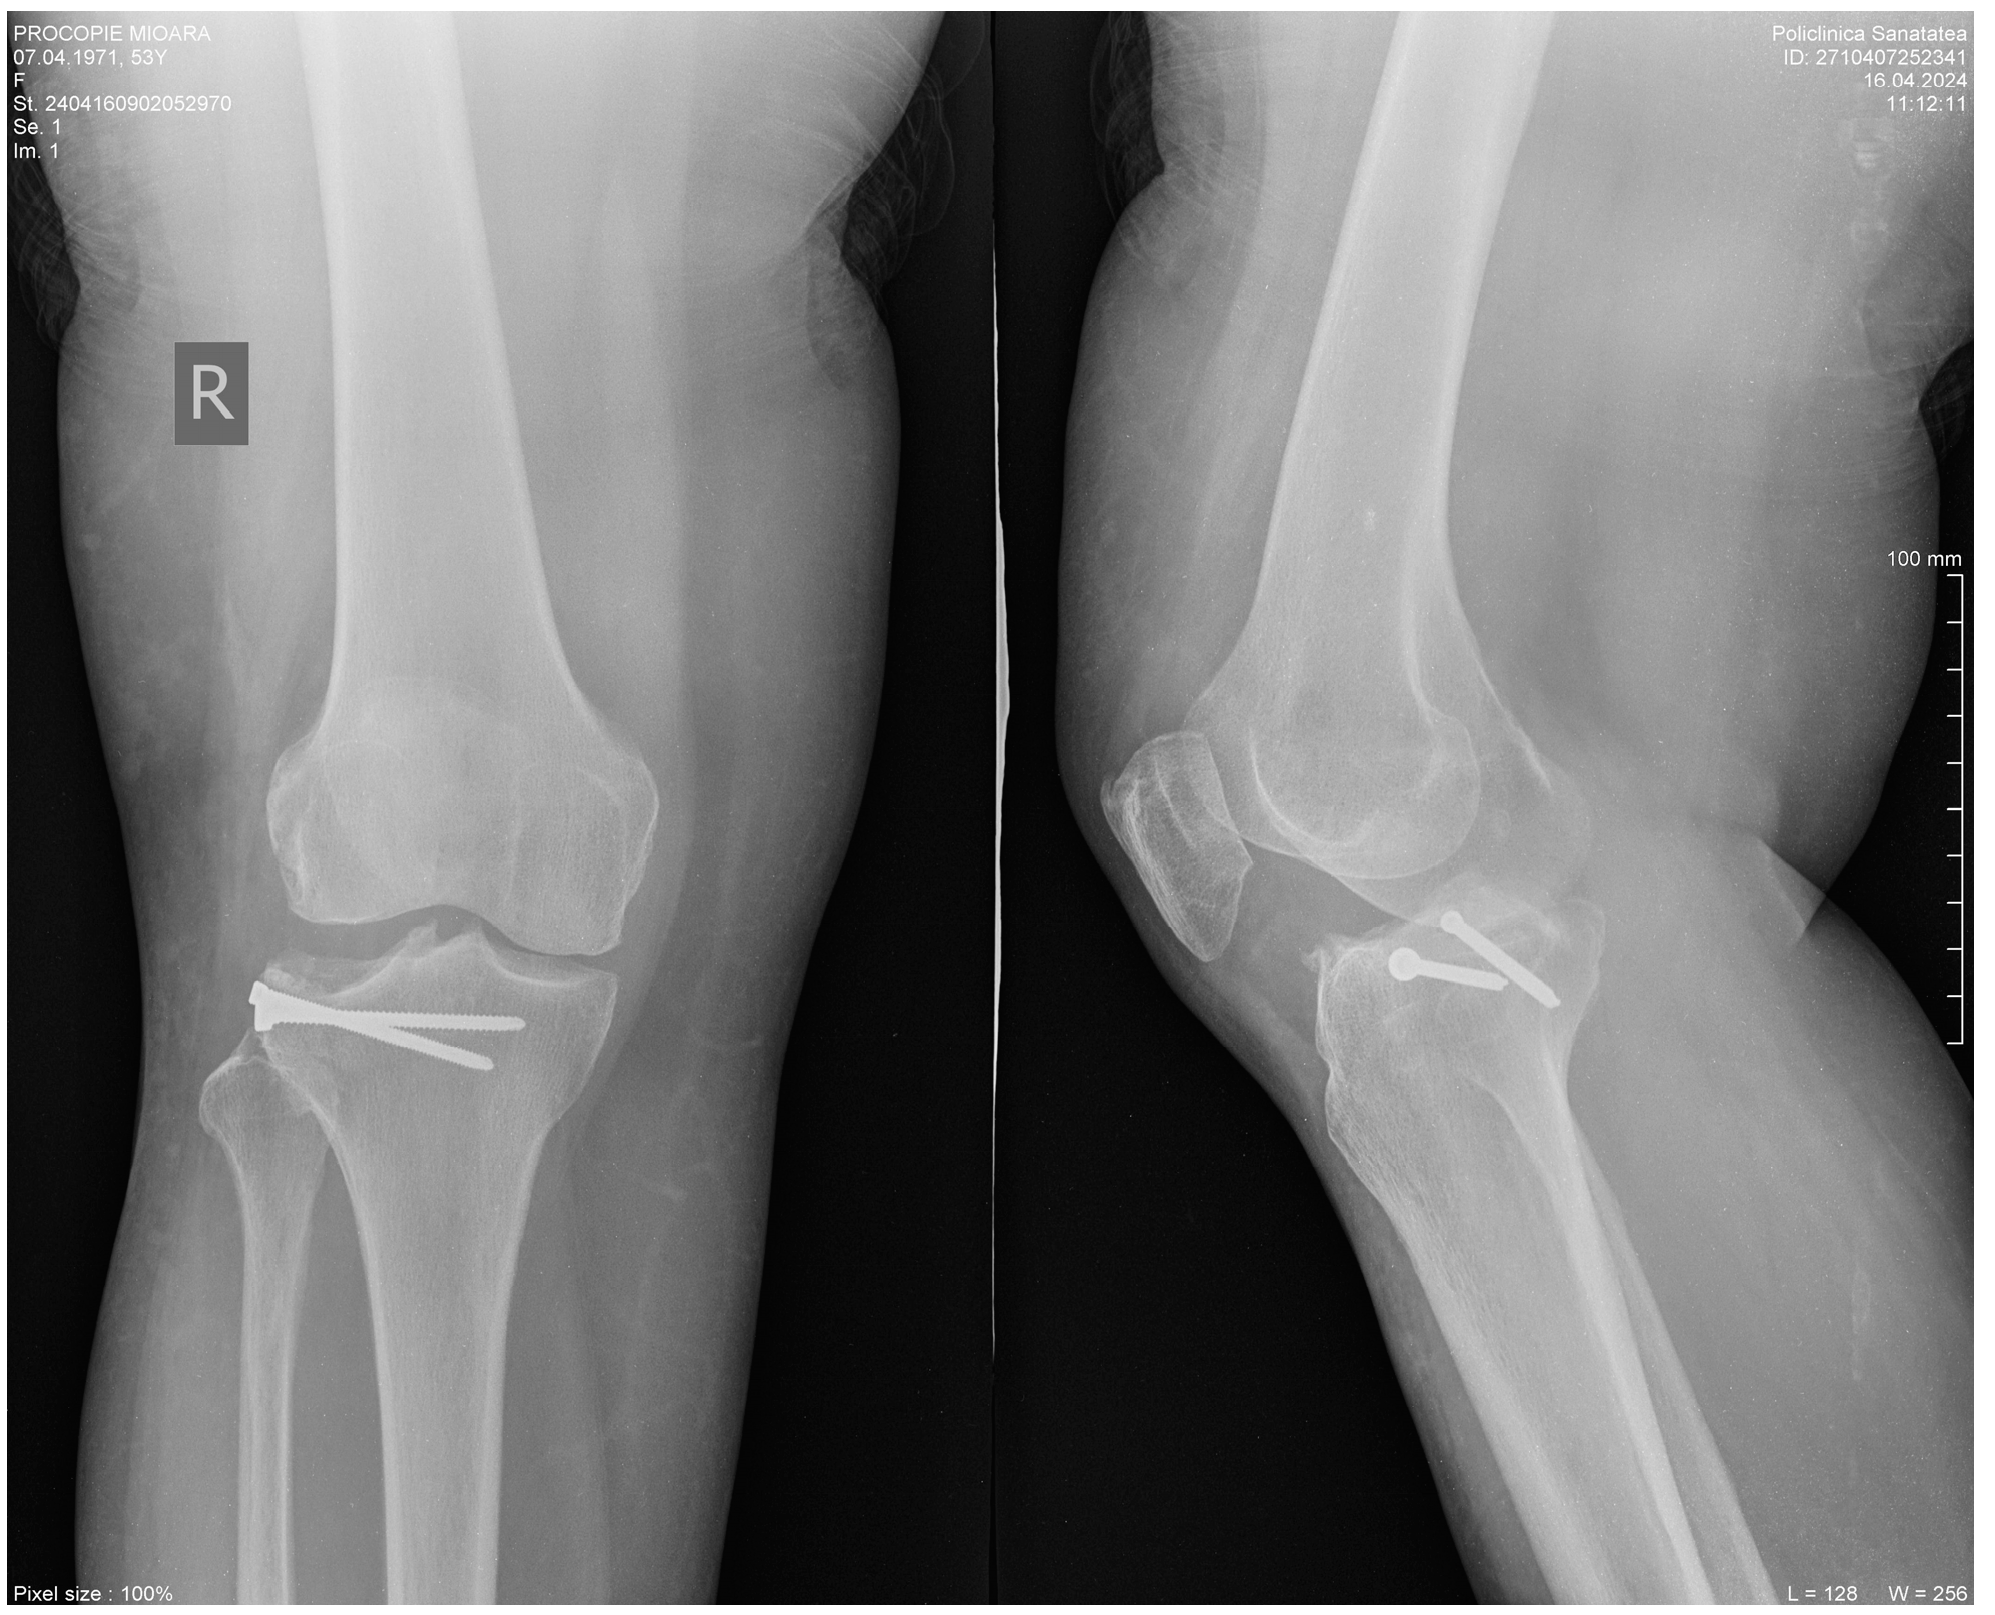

2. Clinical Case Presentation